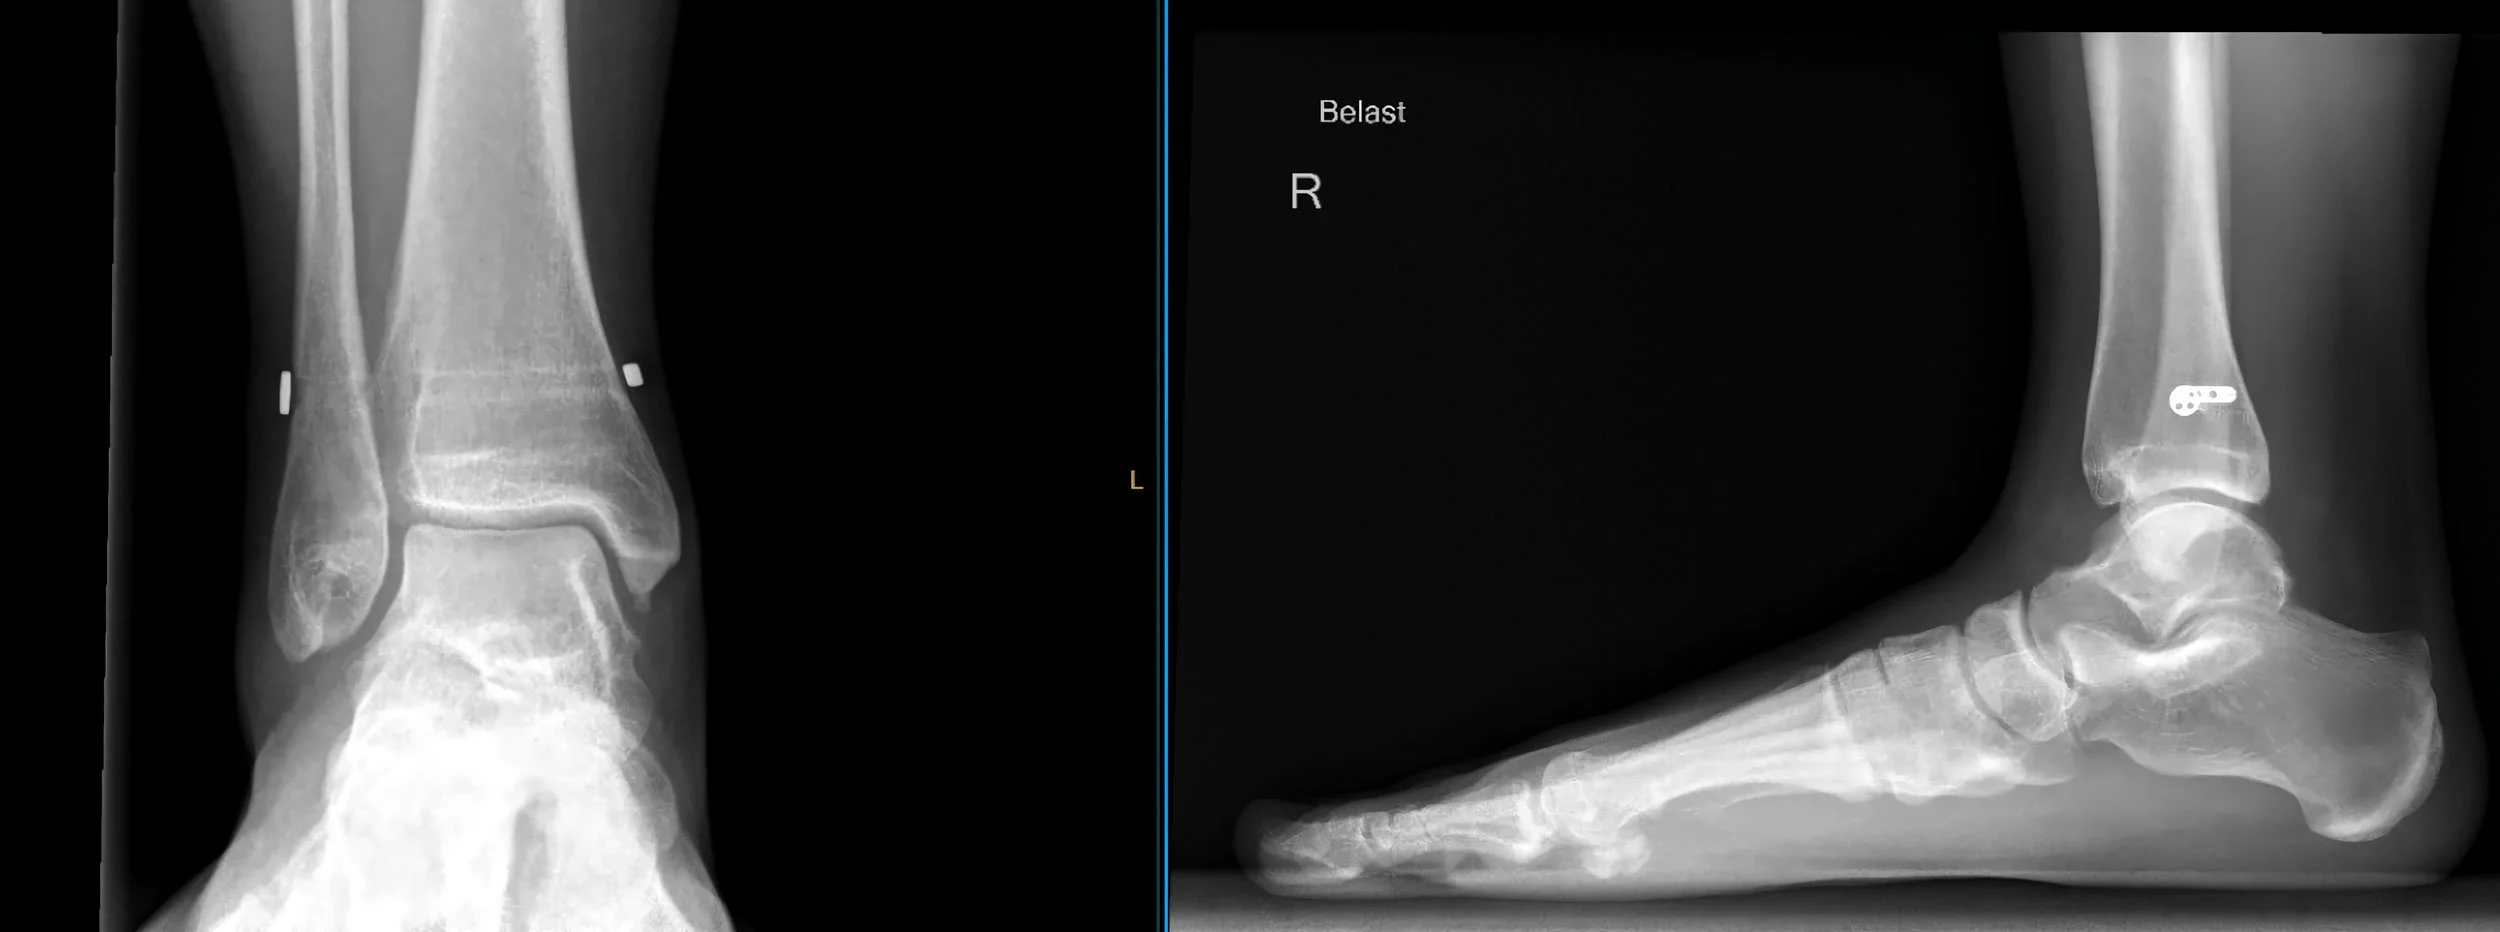

Een syndesmose letsel betreft een beschadiging van de syndesmose, de verbinding tussen de twee onderbeenbeenderen (tibia en fibula) in de onderste helft van de onderbeen. Deze verbinding wordt gevormd door ligamenten en helpt de beenen in plaats te houden en stabiliteit te bieden aan de enkel en het onderbeen.

Bij een ernstige verwikking van de enkel kan naast het scheuren van de enkelbanden ook de syndesmose beschadigd raken. Dit leidt tot een toename van de ruimte tussen het scheenbeen en het kuitbeen, wat we een syndesmose letsel noemen.

De diagnose van een syndesmose letsel wordt meestal gesteld op basis van een medische anamnese, een fysieke onderzoek en beeldvormende technieken zoals röntgenfoto's, MRI of CT-scans. Om te beoordelen of het syndesmose letsel is, zult u vaak een speciaal syndesmosebandje krijgen. Mocht dit helpen, is een operatie mogelijk een optie.